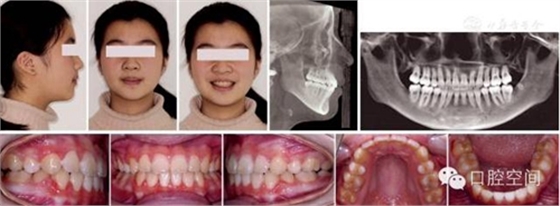

女性,11歲,表現(xiàn)為骨型Ⅱ類錯頜畸形,高角,下頜后縮,上下牙弓前突。X線片顯示正處于生長發(fā)育高峰期。治療前面頜像及X線片見圖2。通過拔除4個第一前磨牙,應用標準方絲弓定向力技術(shù)矯治,并在上頜第一磨牙近中植入種植體。初始弓絲上頜為0.017×0.022英寸不銹鋼方絲(1英寸=2.54 cm),下頜為0.018×0.025英寸不銹鋼方絲,佩戴高位J鉤牽引頭帽12小時/天,先牽引尖牙往遠中,再換用0.020×0.028英寸和0.019×0.025英寸不銹鋼方絲分別彎制關閉曲內(nèi)收上下切牙關閉間隙,在內(nèi)收前牙的同時,對上頜后牙進行垂直向的主動壓低。間隙關閉后應用10-2支抗預備系統(tǒng)直立下頜后牙,上頜始終通過高位J鉤牽引頭帽進行垂直向控制。最后下頜換用0.0215×0.028英寸全尺寸弓絲穩(wěn)定下牙列,使用Ⅱ類牽引和垂直牽引,對Ⅱ類關系進行過矯正。治療中面頜像見圖3。通過25個月的矯治,拆除矯治器,制作佩戴保持器。治療后FMA減少了1°,F(xiàn)MIA和Z角均接近正常值(表3),下頜骨垂直向生長明顯,治療后面型明顯改善,咬合關系良好。治療后面頜像及X線片見圖4,治療前后頭影測量對比圖見圖5。

圖2典型病例治療前面像及X線片

圖4典型病例治療后面像及X線片